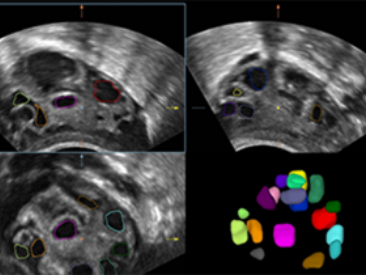

DE11-3E Dual-Volume Solution

DE11-3E Dual-Volume Solution

Images cliniques